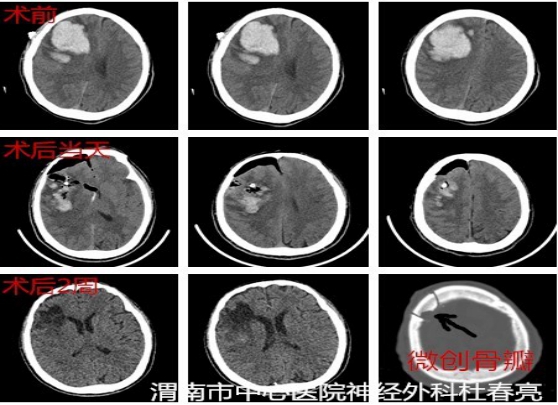

患者王某,男,61岁,入院前突发左侧肢体活动不灵伴意识障碍2小时。查体时显示神志不清,昏迷状态,头颅CT结果显示:右侧基底节区脑出血约40ml。

入院后,在白西民主任、姚胜副主任组织下,党俊涛主任医师及冯毅副主任医师协作,由杜春亮主治医师、王小峰医师及王举医师实施手术。避开重要的血管和神经,取右额平行于中线纵形切口长约4cm,骨窗直径2.5cm,经额叶顺穿刺将套筒准确置入患者大脑深部的血肿腔,建立供内镜通过的微小孔道,再置入圆珠笔芯粗细内镜,以提供良好的照明和视野,很快就准确彻底地清除了深藏脑内的淤血。术后CT显示血肿清除干净,目前患者神志清楚,已康复出院。